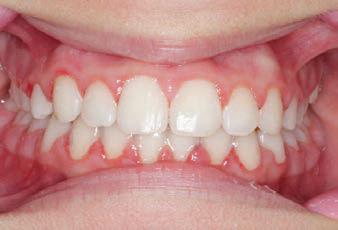

FINAL - 10/10/19 - Appliances removed AFTER

PROGRESS 7 - 10/10/19 - Final day in SLX 3D Clear Brackets BEFORE